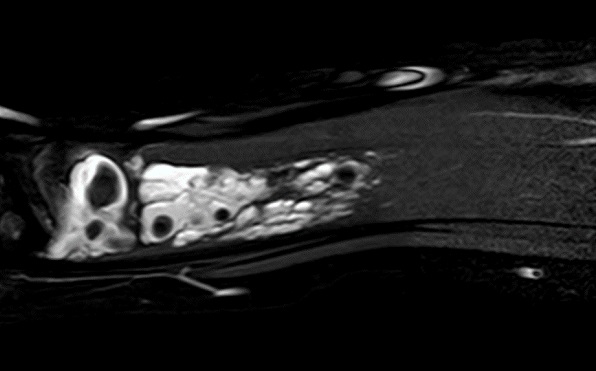

Se solicita radiografía donde se visualizan estructuras calcificadas compatibles con flebolitos (Fig. 1), no se objetivan líneas de fractura.

Figura 1. Radiografía

En cuanto a técnicas de imagen, la radiografía detecta la presencia de flebolitos orientando el diagnóstico desde Atención Primaria. La lesión vascular de flujo lento se confirmará mediante ecografía Doppler. Es fundamental remitir a cirugía vascular para completar estudio mediante resonancia magnética que ayude a definir la extensión y decidir el abordaje adecuado.